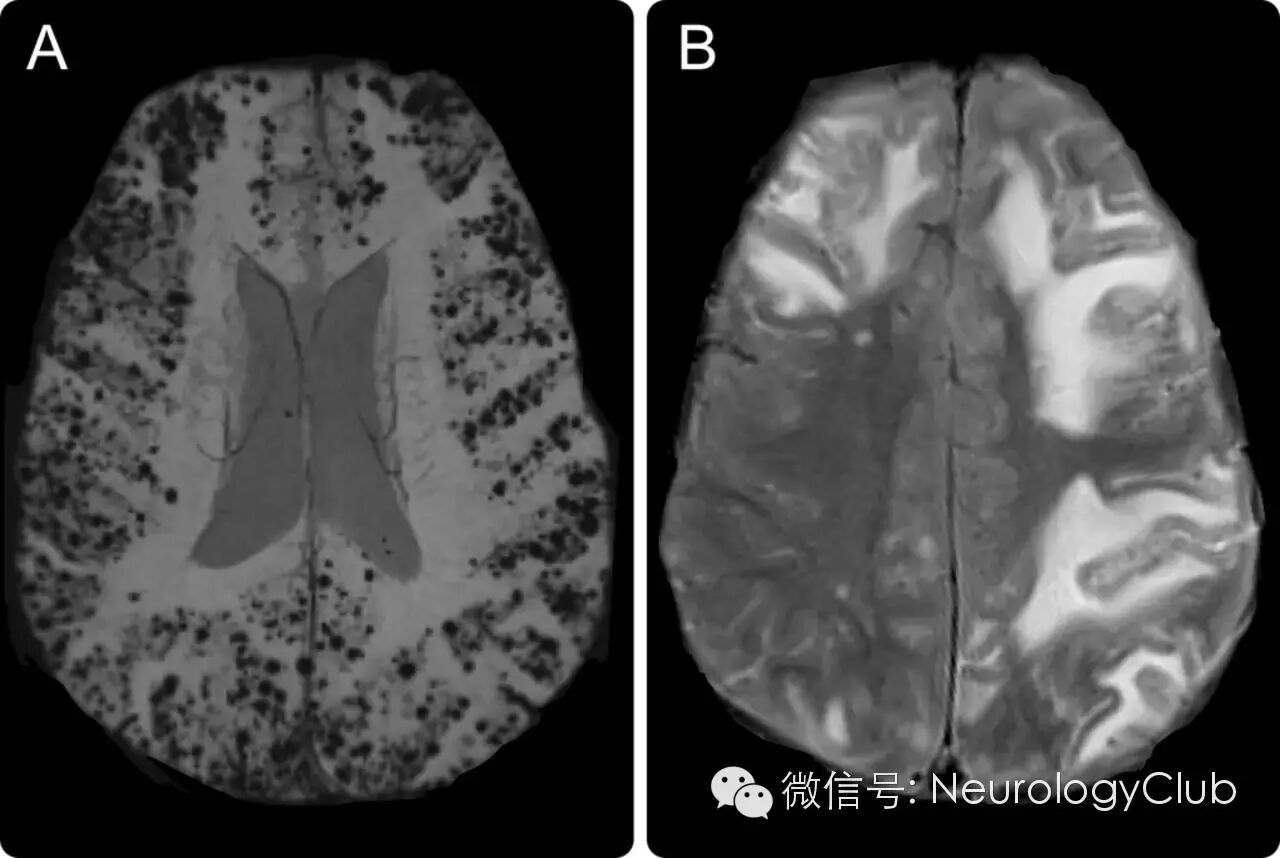

(59岁男性。A:SWI上可见脑叶弥漫微出血灶;FLAIR提示皮质下双侧不对称性高信号病灶)

A-B:治疗前的FLAIR和T2*WI;C-D:免疫抑制治疗后FLAIR和T2*WI提示病灶明显减少;E-F:脑实质和柔脑膜血管壁淀粉样蛋白沉积[Aβ4染色,×10;刚果红染色,×10];G:柔脑膜血管周围淋巴细胞浸润[CD3染色,×10]

A-B:治疗前的FLAIR和T2*WI;C-D:免疫抑制治疗后1月复查FLAIR和T2*WI提示病灶明显减少;E:脑实质和柔脑膜血管壁淀粉样蛋白沉积[刚果红染色,×10];F:血管壁[箭]和一些淀粉样蛋白斑块[箭头,Aβ4染色,×10];G:淀粉样蛋白沉积的血管周围可见T3淋巴细胞浸润[CD3染色,×40]